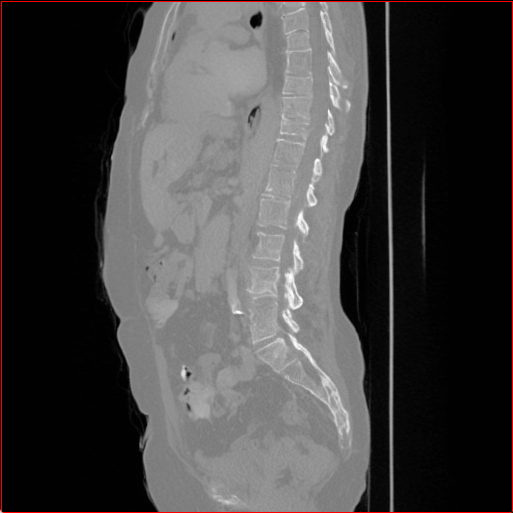

MAISI-v2 generalizability:

Figure 4 shows qualitatve results of MAISI-v2 ControlNet for different body regions and voxel sizes.

Head Region

1.1×1.1×1.11.1\times 1.1\times 1.1

mm

256×256×256256\times 256\times 256

Chest Region

1×1×11\times 1\times 1

384×384×384384\times 384\times 384

Abdomen Region

1×1×0.71\times 1\times 0.7

512×512×768512\times 512\times 768

Refer to caption

Figure 4: MAISI-v2 segmentation-guided results for small to large volume size and three different regions.